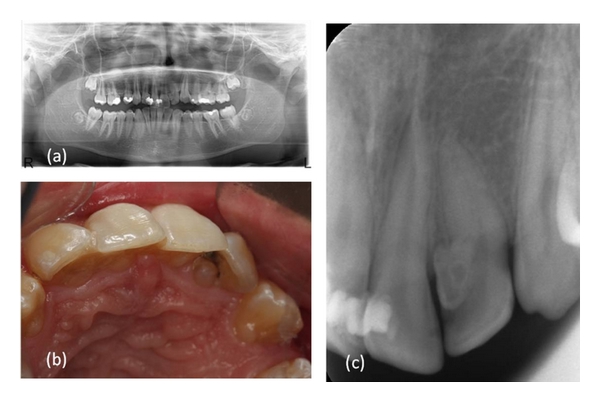

A 16-year-old male patient who did not have any problems in his medical history was referred to the Faculty of Dentistry, University of Kocaeli, for his dental treatments. After clinical and radiologic evaluations, we detected caries on the maxillary left lateral incisor which had unusual anatomy (Figures 1, 1, and 1). The initial periapical radiographic examination revealed that the maxillary left lateral incisor showed an abnormal morphology with an invagination (Oehlers’ type II). During the removal of deep dentin caries, the pulp tissue was exposed. The patient was anesthetised, and rubber dam was placed and stabilised using widgets. The main canal and invaginated canal communicated at the middle of the root. The working length was established by a Raypex 5 apex locator (VDWEndodontic Synergy, Munich,Germany). A radiograph showed the fusion of the main canal and invagination (Figure 2). The root canals were prepared with stainless steel H files (Mani Inc., Tochigi, Japan) using a step-back technique. The irrigation was copious throughout with a 2.5% sodium hypochlorite solution, and EDTA (MD-ChelCream, META BIOMED, Chungbuk, the Republic of Korea) was used for chelation. The root canals were dried with paper points and (Precise Dental, Zapopan, Mexico) obturated with a lateral condensation technique with a 0.02 tapered gutta-percha (Diadent, Choongchong Buk Do, the Republic of Korea) and an AH plus (Dentsply De Trey GmbH, Konstanz, Germany) root canal sealer (Figure 3). A two-step self-etch adhesive system (Clearfil SE Bond, Kuraray Medical Inc., Japan) was used in order to perform a restorative treatment. The teeth were restored with a nanofilled resin composite (CLEARFIL MAJESTY Esthetic, Kuraray Medical Inc., Japan). Six months later, the tooth was asymptomatic and all clinical findings were within normal limits (Figure 4).